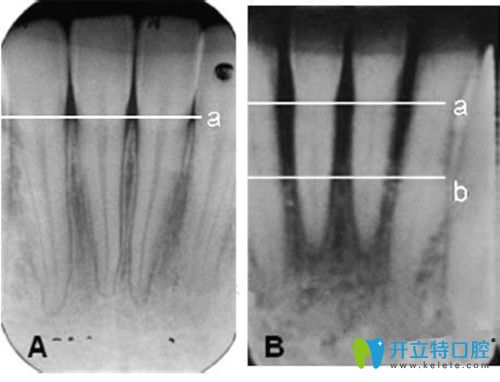

牙槽骨小于幾毫米不能種牙?怎么判斷牙槽骨薄,這篇就夠了

牙槽骨萎縮人工種植牙發(fā)布時間: 2025-04-25

種牙如種樹,骨量充足是種牙必備條件,如果你的牙槽骨萎縮,種牙前也許你需要先去植骨。那么怎么判斷牙槽骨???